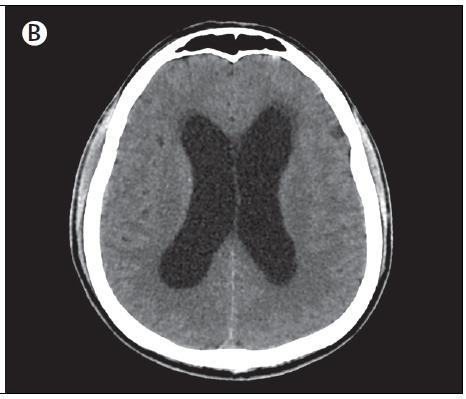

脑水肿CT,脑梗死ct

入院第5天患者出现急性定向力障碍和颈部僵硬症状,但无视神经乳头水肿

头颅ct显示去骨瓣减压之后继续nivolumab治疗,发展成严重脑水肿和

患者出院前ct复香,脑水肿基本消退,神志请,能言语,经口进食,院外康复.

图6.头颅ct提示脑水肿及中线移位较前减轻